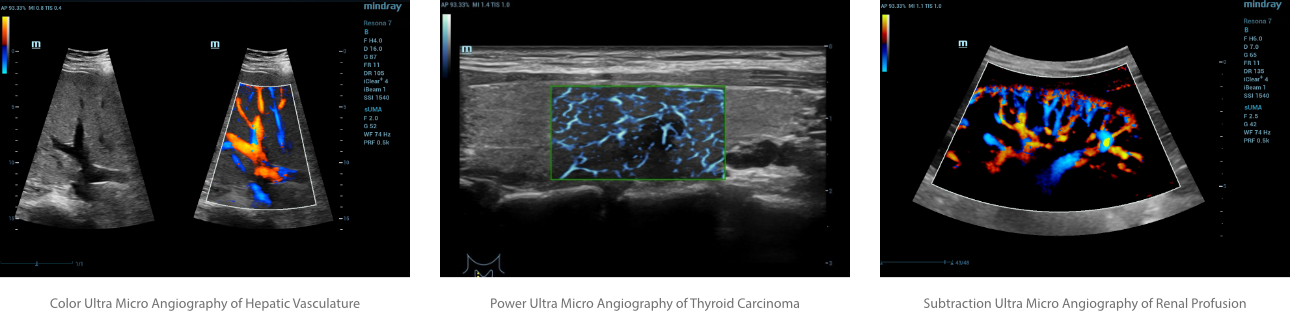

Ultra Micro Angiography (UMA)

is an innovative method of visualizing low-velocity micro-vascular flow states. UMA compensates for the limitations of traditional flow modes in detecting slow flow. It allows for visualization of the supply vessels surrounding diseased tissues, further enhancing diagnostic capabilities for lesion detection and characterization.

• Color UMA – UMA with a traditional color map overlay for improved sensitivity

• Power UMA – UMA with Power Doppler sensitivity, also available in bidirectional mode

• Subtraction UMA – UMA combined with tissue subtraction for enhanced evaluation of vessels separate from grayscale imaging